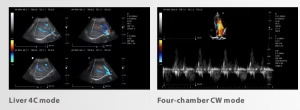

| Modos de imagen | B, Dual-B, Quad-B, M, B+M, 2CFM (Color Flow), PW (Pulsed Wave), CW (Continuous Wave), PDi, THI |

Diagnóstico avanzado y versátil: gracias a sus modos 2D, Doppler color, PW y CW, el CU45 permite una amplia gama de estudios en cardiología, ginecología, abdominal, vascular y veterinaria.